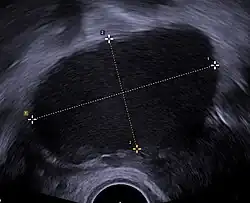

![]() Transvaginal ultrasonography showing a 67 x 40 mm endometrioma as distinguished from other types of ovarian cysts by a somewhat grainy and not completely anechoic content. | |